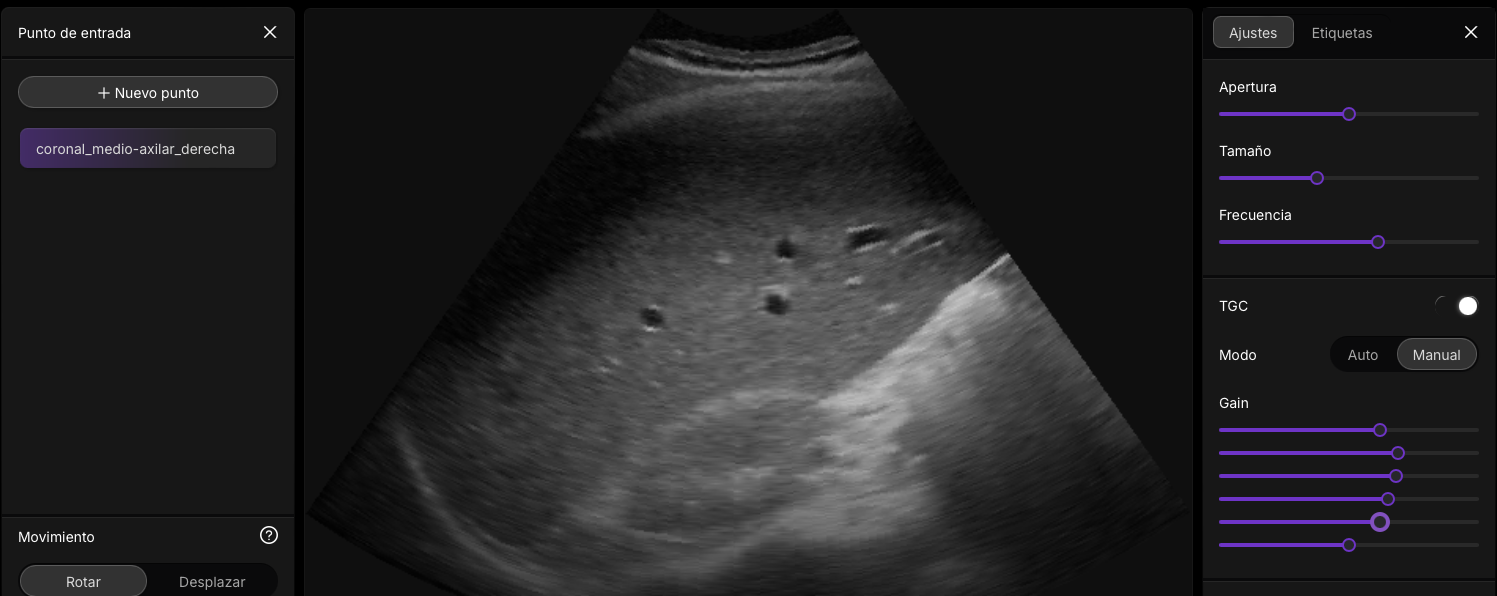

👉📟 Ir a Imagineus®.

Interacción Sonido con tejidos: Just do It!

Imagenus 1: Ejemplo de imagen ecográfica mostrando estructuras hiper, hipo e isoecogénicas (calota craneal hueso, grasa, lipoma)

👉 Al pulsar sobre la imagen accederás a un jugable docente.